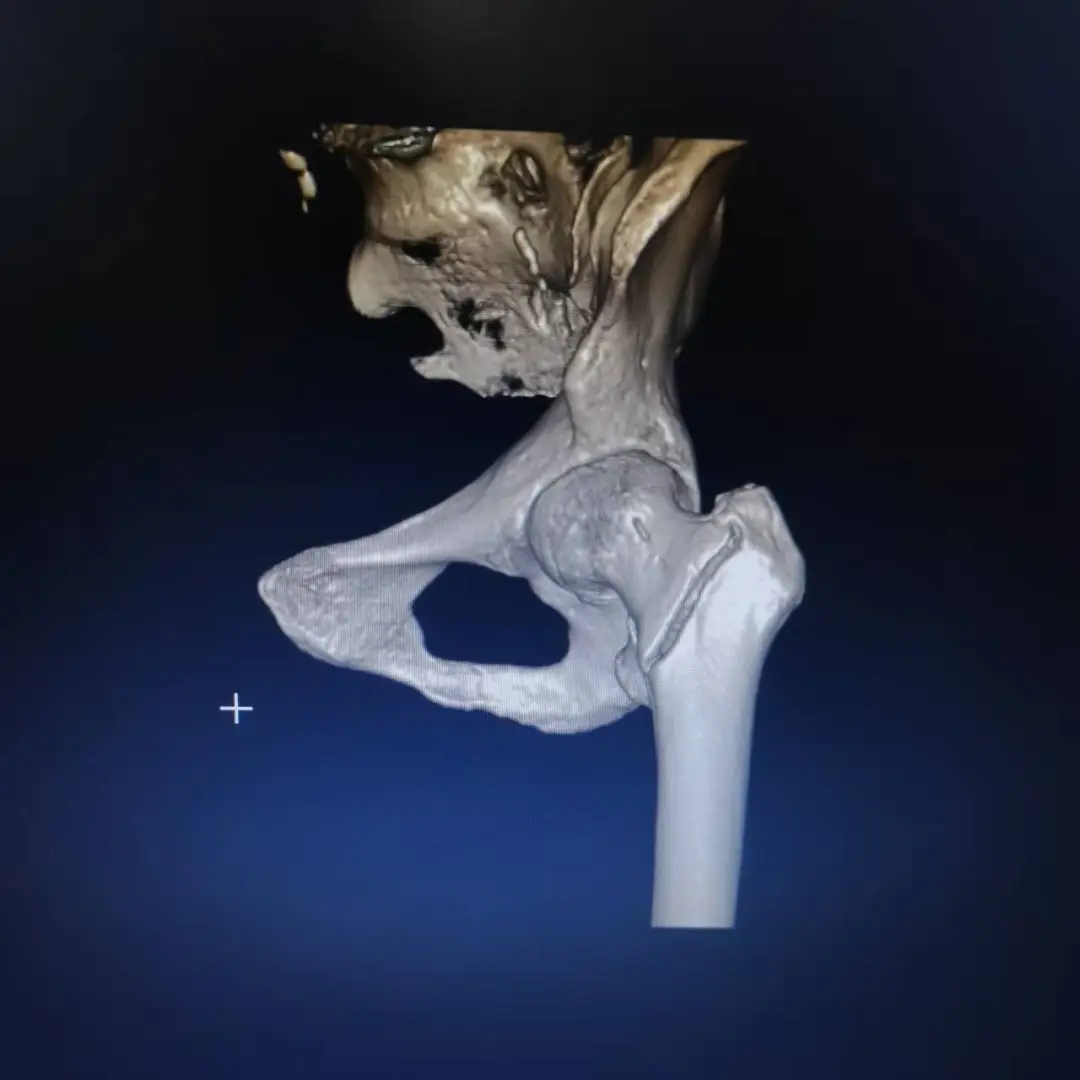

73歲的周阿姨(化名)因雨天路滑在院子摔倒,左髖部劇痛且活動受限。當(dāng)?shù)卦\所按常規(guī)給予膏藥和止痛藥治療,但疼痛反而加重。后經(jīng)拍片檢查,診斷為“左股骨轉(zhuǎn)子間骨折”——即髖部骨折的一種,需要手術(shù)治療。

經(jīng)過系統(tǒng)術(shù)前調(diào)理,患者電解質(zhì)紊亂得到糾正,心功能趨于穩(wěn)定。在多學(xué)科團(tuán)隊(duì)評估后,最終排除絕對手術(shù)禁忌癥,確定手術(shù)方案為“左側(cè)股骨髓內(nèi)針內(nèi)固定術(shù)”。該術(shù)式創(chuàng)傷小、固定牢,利于患者早期活動,非常適合高齡患者。